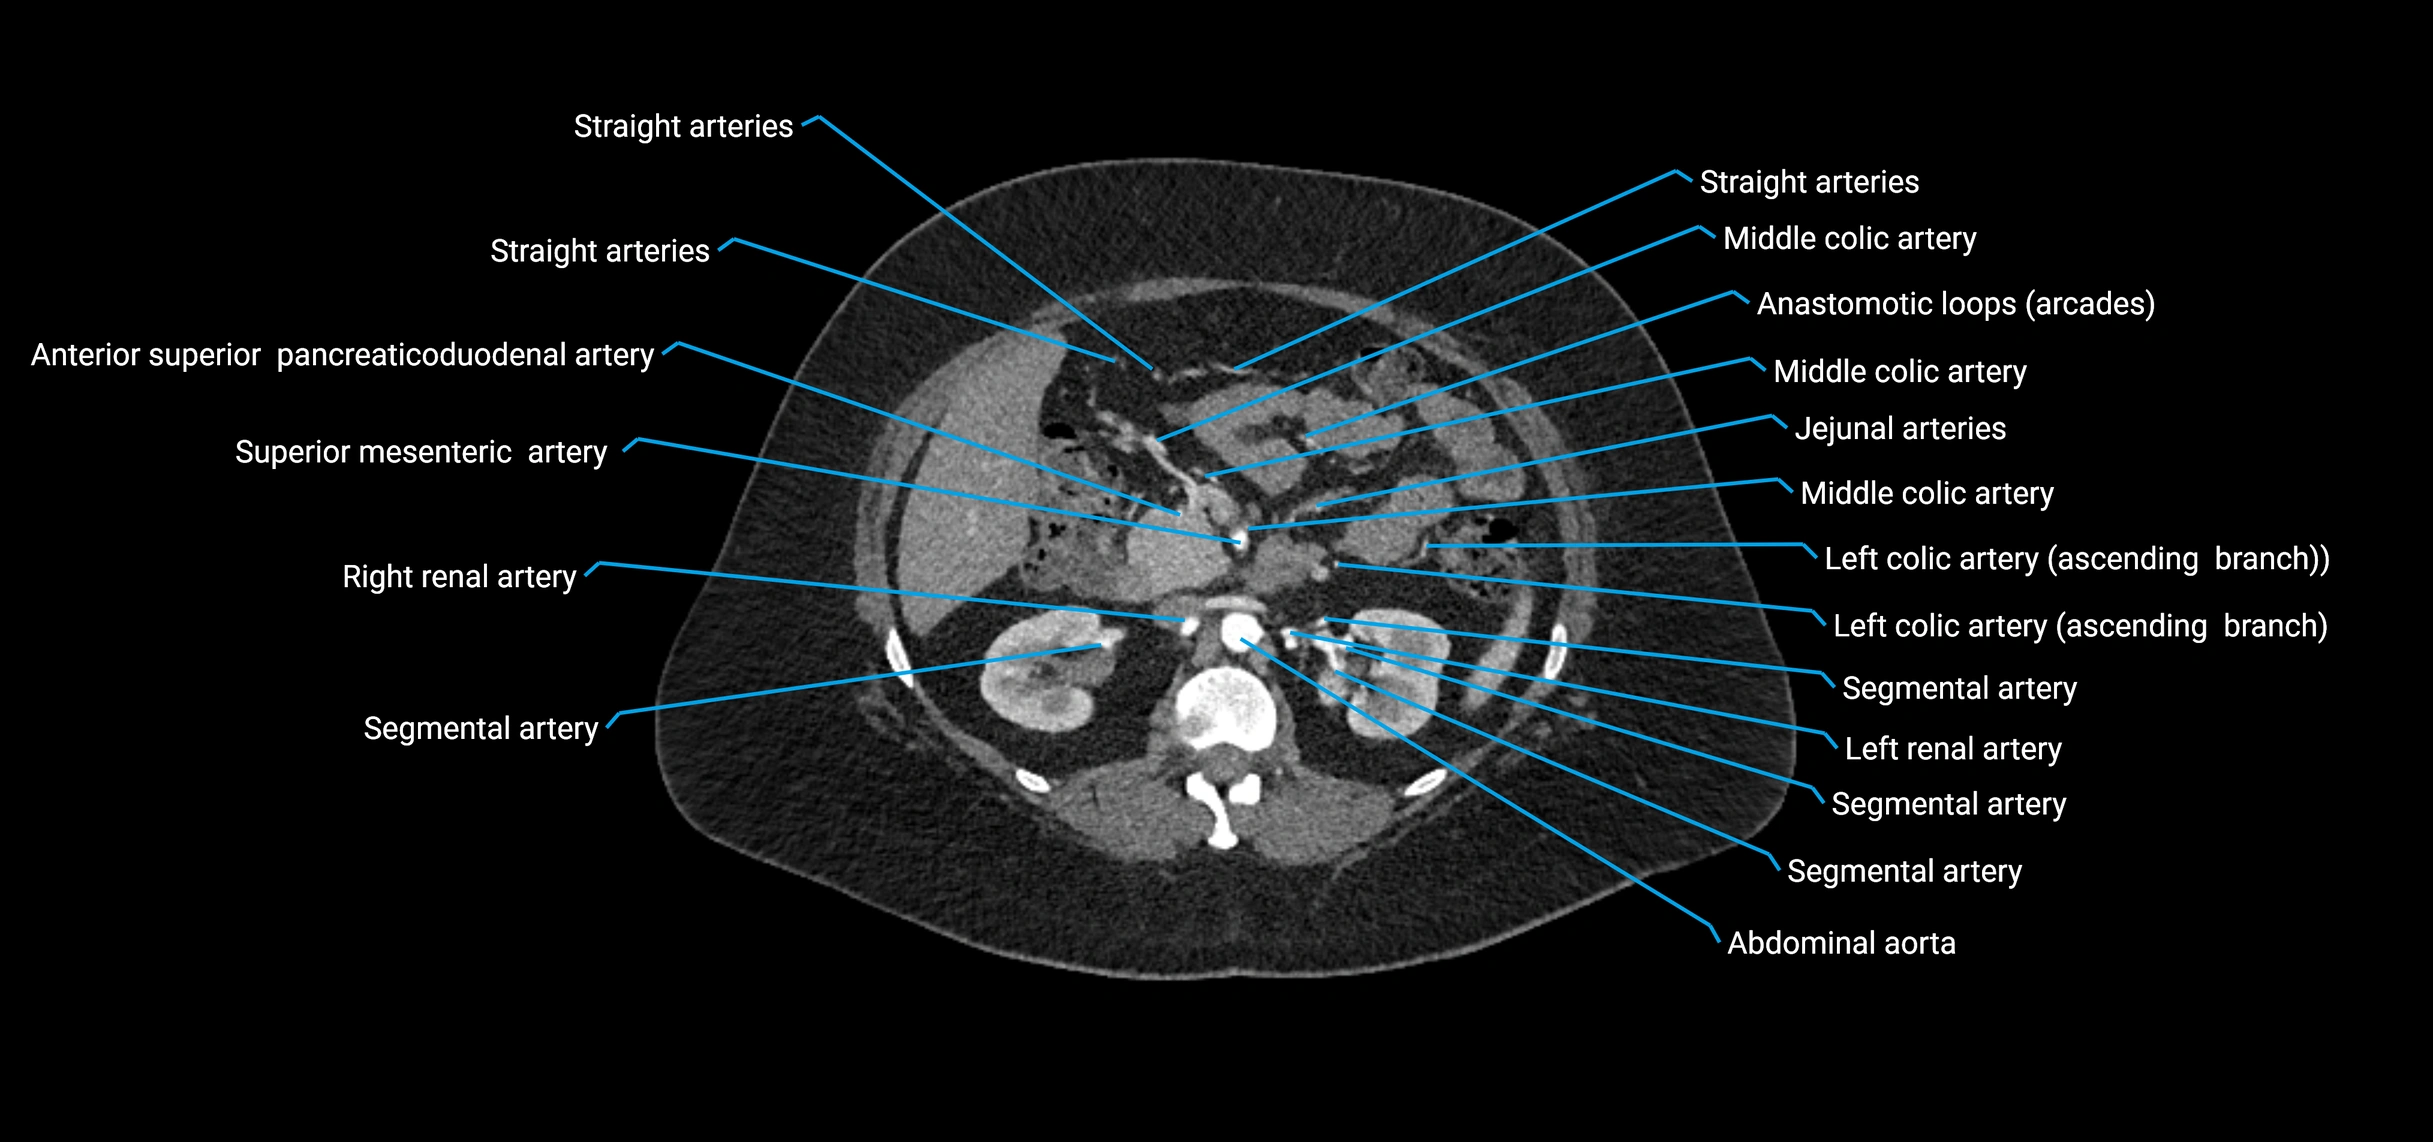

Contrast-enhanced CT (CTA):

• Gold standard for abdominal aortic imaging

• Provides excellent detail of lumen, wall, aneurysm, thrombus, and branch vessels

• Multiplanar and 3D reconstructions help in aneurysm measurement, stent graft planning, and dissection evaluation

• Detects acute rupture, traumatic injury, or occlusion with high sensitivity